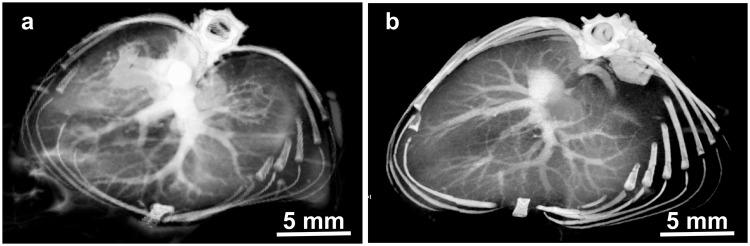

Standard clinical X-ray contrast agents are small iodine-containing molecules that are rapidly cleared by the kidneys and provide robust imaging for only a few seconds, thereby limiting more extensive vascular and tissue biodistribution imaging as well as optimal tumor uptake. They are also not generally useful for preclinical microCT imaging where longer scan times are required for high resolution image acquisition. We here describe a new iodine nanoparticle contrast agent that has a unique combination of properties: 20 nm hydrodynamic diameter, covalent PEG coating, 40 hour blood half-life, 50% liver clearance after six months, accumulation in tumors, and well-tolerated to at least 4 g iodine/kg body weight after intravenous administration in mice. These characteristics are unique among the other iodine nanoparticles that have been previously reported and provide extended-time high contrast vascular imaging and tumor loading. As such, it is useful for preclinical MicroCT animal studies. Potential human applications might include X-ray radiation dose enhancement for cancer therapy and vascular imaging for life-threatening situations where high levels of contrast are needed for extended periods of time.

标准的临床 X 射线造影剂是含有碘的小分子,它们会被肾脏迅速清除,只能提供几秒钟的强成像效果,从而限制了更广泛的血管和组织生物分布成像以及最佳的肿瘤摄取。它们通常也不适用于临床前 microCT 成像,因为 microCT 成像需要更长的扫描时间来获取高分辨率图像。我们在这里描述了一种新型的碘纳米颗粒造影剂,它具有独特的组合特性:20nm 的水动力直径、共价 PEG 涂层、40 小时的血液半衰期、6 个月后 50%的肝脏清除率、在肿瘤中的积累,以及在小鼠中静脉注射至少 4g 碘/kg 体重后可耐受。这些特性在以前报道的其他碘纳米颗粒中是独一无二的,提供了长时间的高对比度血管成像和肿瘤负荷。因此,它可用于临床前 MicroCT 动物研究。潜在的人类应用可能包括增强癌症治疗的 X 射线辐射剂量和用于危及生命的情况的血管成像,这些情况下需要长时间的高对比度。